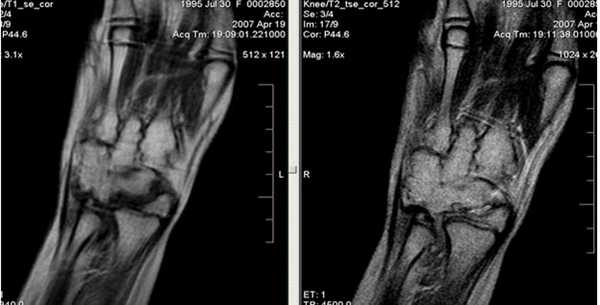

Ревматоидный артрит. Субхондральные эрозии, гипертрофия синовиальной оболочки.

Ревматоидный артрит. Анкилозирование костей запястья, деструкция эпифизов лучевой и локтевой костей.

Синдром поражения суставов

Большинство изменений локтевого сустава сопровождается симптомами сопутствующего экссудативного синовита; его выраженность зависит от тяжести травм. На МРТ выявляется суставной выпот. Кроме того, иногда определяется отек костного мозга в субхондральных отделах эпифизов костей, отек периартикулярных мягких тканей.

Ревматоидный артрит III стадия выпот в полости сустава (1), грубое эрозирование субхондрального слоя головки плечевой кости (2), фрагментация суставной губы гленоида.

Ревматоидный артрит, II ст. субхондральные жидкостные кисты в эпифизе плечевой кости (1), краевые узуры лучевой кости.

Ревматоидный артрит, III ст. субхондральные эрозии (1) и краевые узуры (2) дистального эпифиза плечевой кости, наличие суставного выпота (3) и массивная гипертрофия синовиальной оболочки (4).